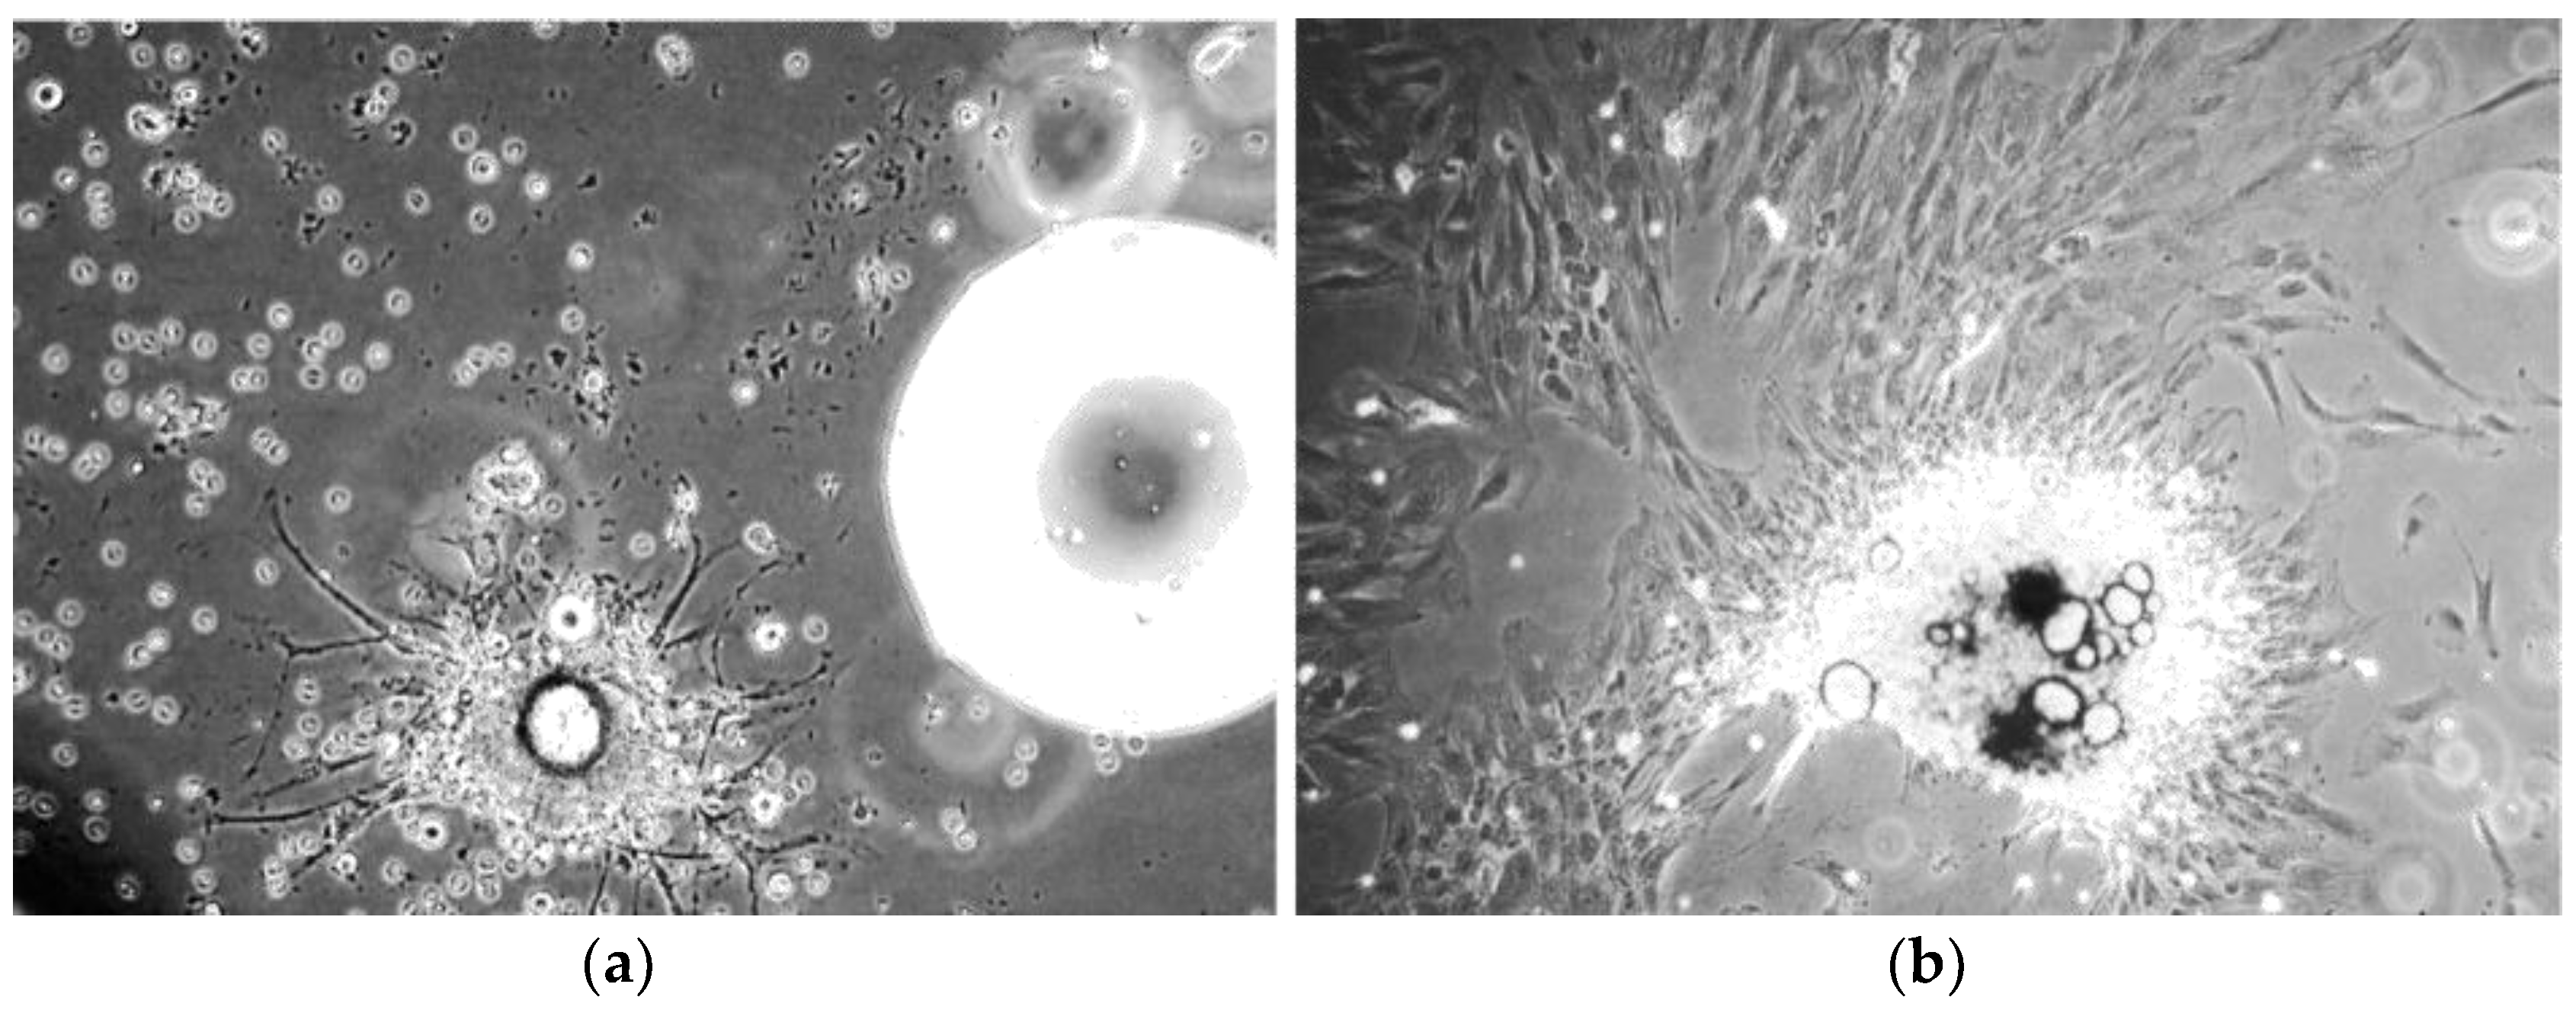

MSC suspensions from each patient sample were seeded at a concentration of 2 × 104 cells per hanging drop well and were incubated for 24 h at 37 °C and 5% CO2. Sphere forming capacity was assessed in 12 replica wells for each of the three populations studied. Figure 5a demonstrates a mesensphere grown using the BM001 primary cells imaged 24 h after seeding at 10× magnification.

Average sphere size after 24 h was very consistent between the replicas across the sample populations. The diameter of mesenspheres ranged from 212 µm to 253 µm in greatest dimension. All samples tested displayed excellent self-assembly properties indicative of the viable MSC phenotype.

In addition to culturing mesenspheres in the 3D-Perfecta Hanging Drop Plate, an in-house device (drop-well) was fabricated that allowed for the culture of much larger mesenspheres. The in-house device, which is made from a cap of a 1.5 mL microcentrifuge tube glued to a 10 cm tissue culture lid, enabled the cultured spheroids to reach sizes up to of 4.6 mm. These larger self-aggregated stem-cell colonies, not only demonstrated similar internal heterogeneity as their smaller counterparts grown in the Perfecta drop plates, but could theoretically be shaped and re-implanted as is at the site of injury without the need for additional scaffolding material, due to their large size. Figure 5b shows the in-house device with a large active stem-cell culture.

Figure 5. Phase contrast microscope images of hBM-MSCs mesenspheres. (a) Microscope image of a BM001 hBM-MSCs mesensphere (247 µm largest diameter) grown using the 96-well Perfecta 3D drop plate (100× magnification); (b) Image of a BM001 hBM-MSCs mesensphere (4.6 mm largest diameter) grown using the in-house drop-well device.